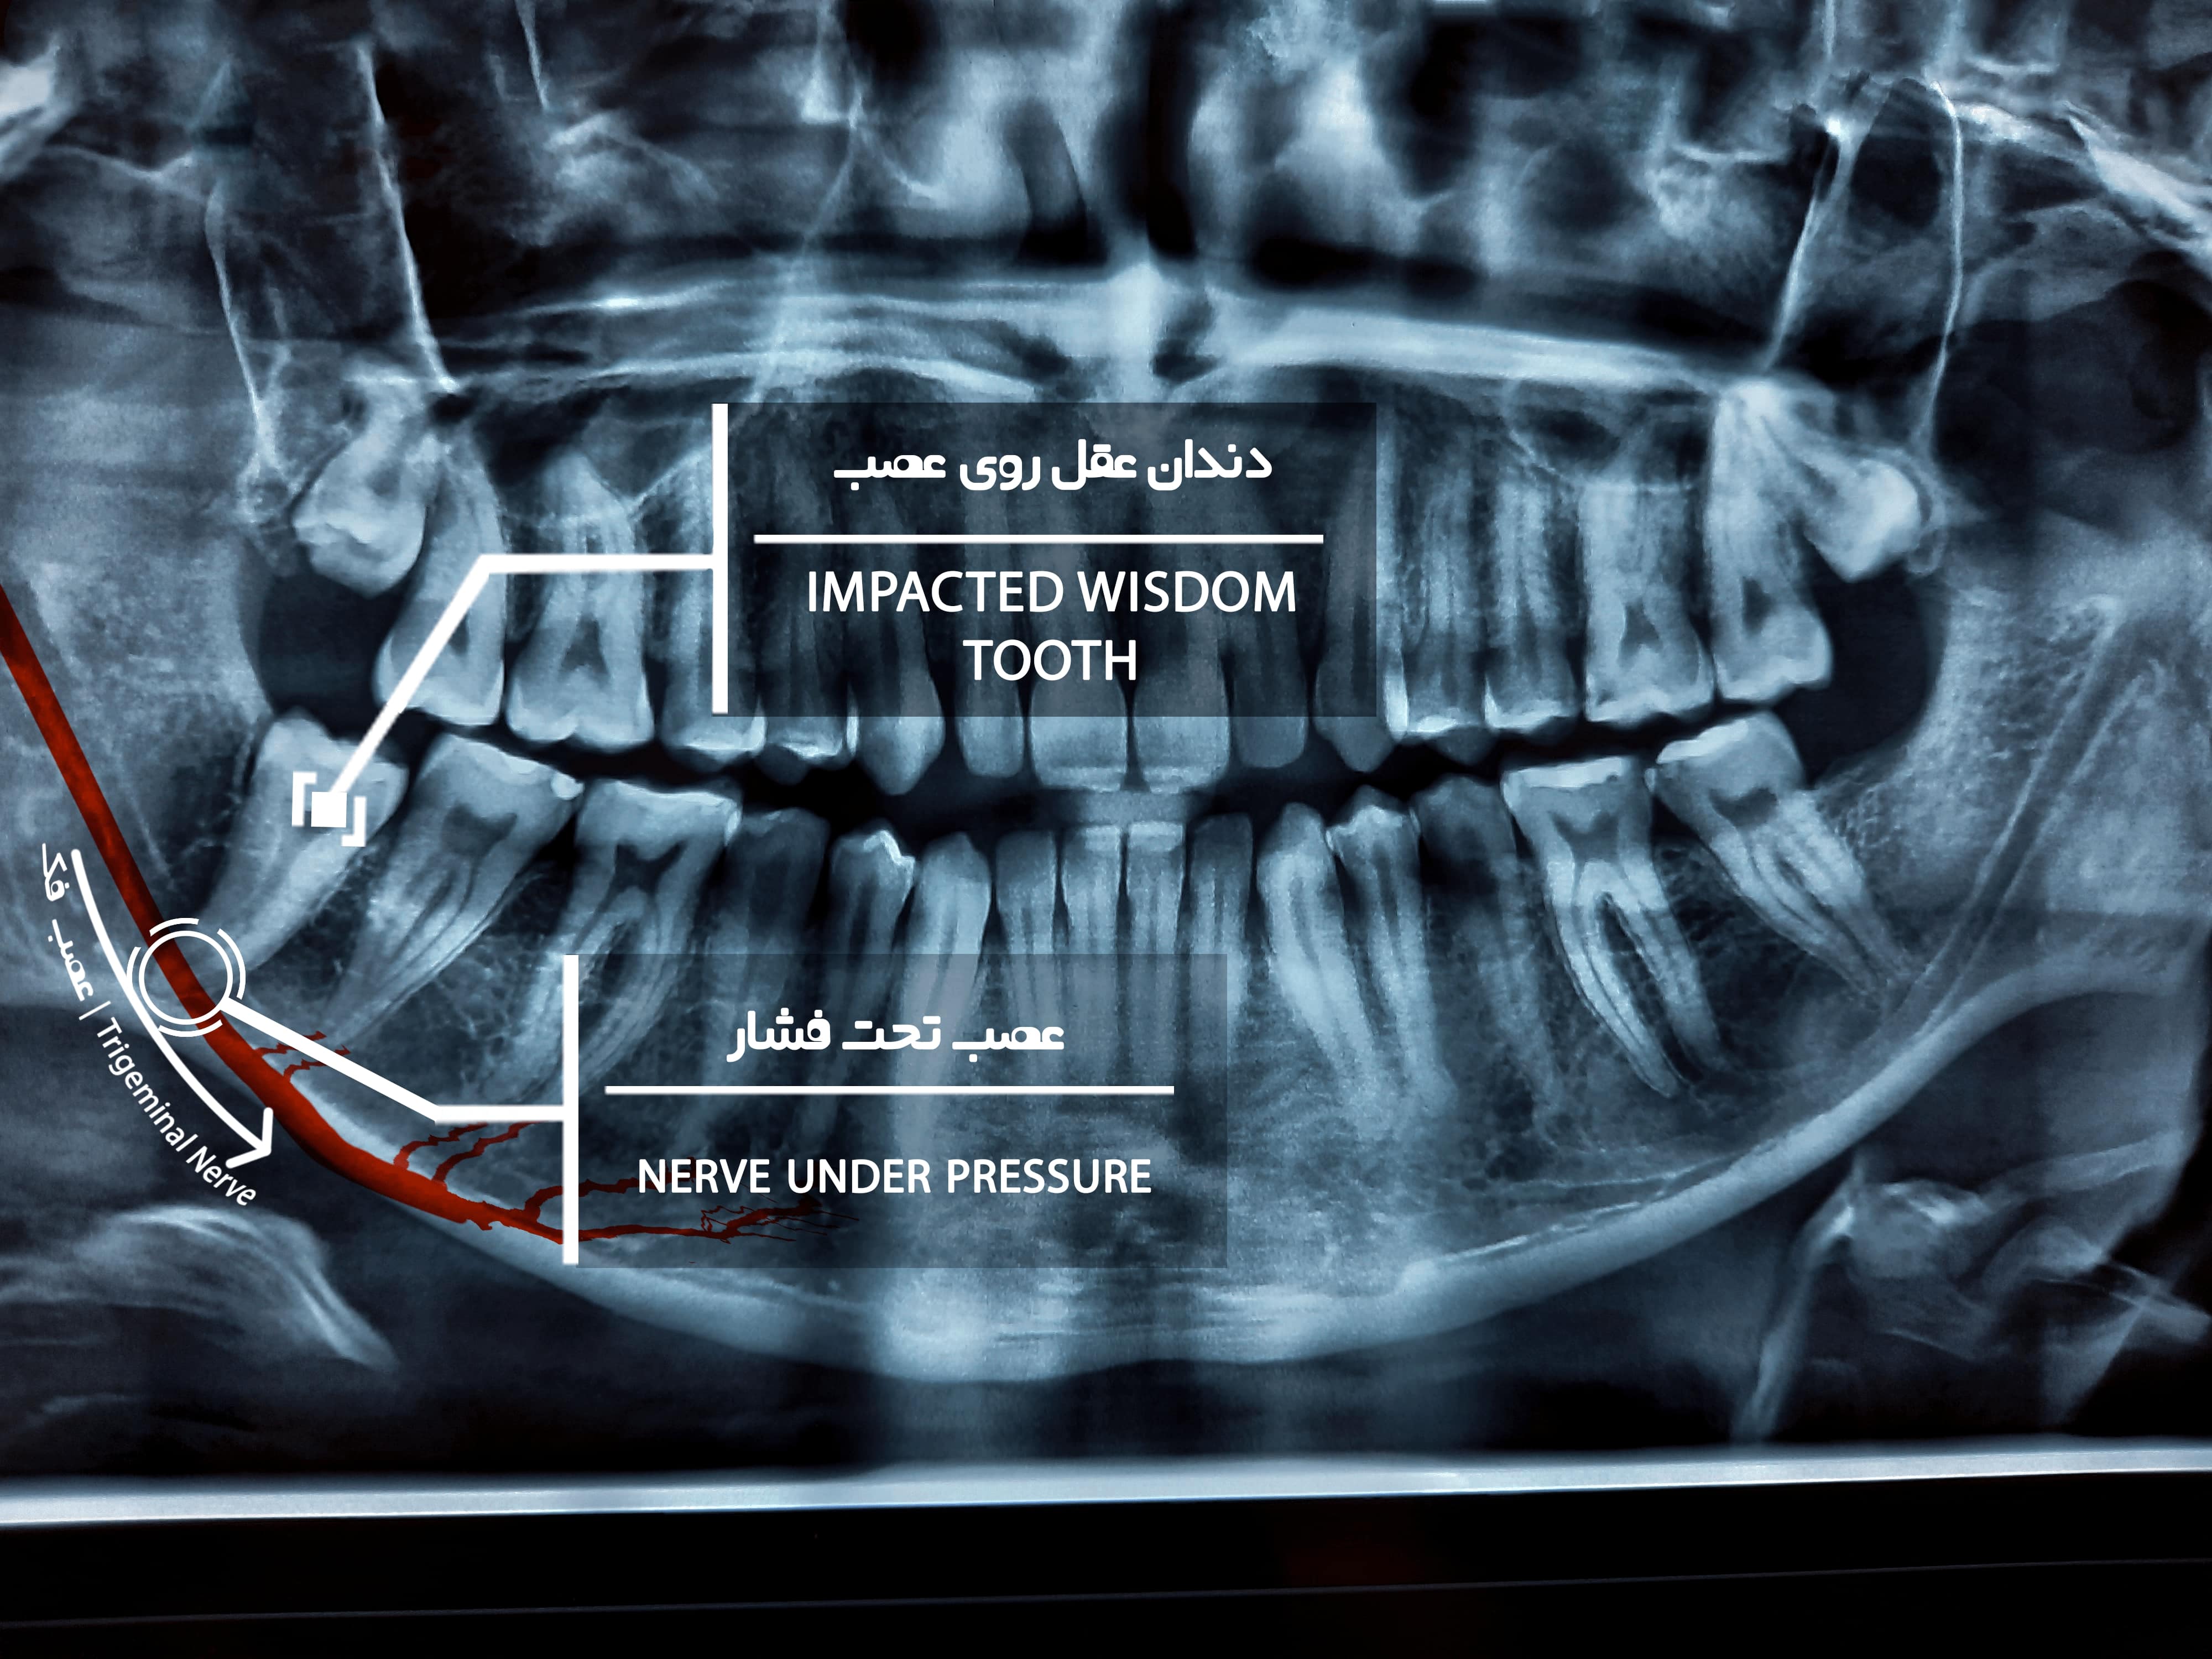

استفاده از لیزر دندانپزشکی برای از بین بردن بی حسی فک

یکی از موارد مهم از کاربرد های لیزر در دندانپزشکی، ترمیم اعصاب ناحیه ای است، که یکی از عارضه های احتمالی بعد از کشیدن دندان عقل نزدیک به عصب در فک پایین است. در این شرایط به کمک لیزر دندانپزشکی میتوان اعصاب نواحی آسیب دیده را را ترمیم و التهاب سلول ها را متوقف کرد. البته توجه داشته باشید که مهم ترین نکته در فرایند لیزر تراپی مراجعه منظم و به موقع جهت درمان است، زمان طلایی مراجعه به دندانپزشک سه روز بعد از جراحی است. و روند لیزر تراپی در 10 جلسه منظم یک روز در میان انجام میگردد.

در این شرایط لیزر موجب افزایش گردش خون، کاهش تورم و التهاب ناشی از جراحی میگردد، از سوی دیگر انرژی لیزر توسط ساختارهای سلولی جذب می شود و موجب تحریک فعالیت سلولی و سلول های عصبی شده و در نتیجه افزایش روند بهبودی میگردد.